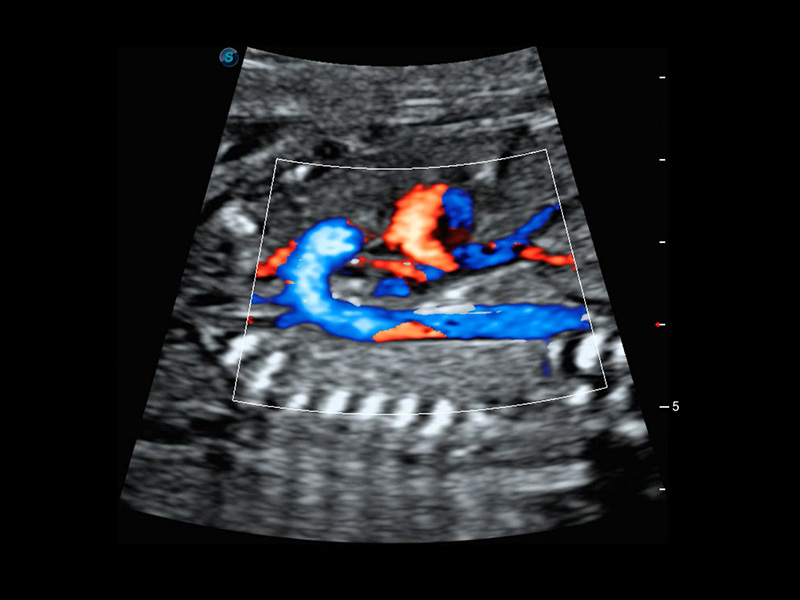

4D HyCoSy mit SPI

Die farbkodierte Hysterosalpingo-Kontrastsonografie (HyCoSy) ist eine proprietäre Funktion auf P60 Exp, die die Ankunftszeit von Kontrastmitteln in verschiedenen Teilen der Gebärmutter, der Eileiter und der Eierstöcke klar demonstrieren kann. Dadurch erhalten Kliniker starke und zuversichtliche Beweise, um die Tubenpatenz bei subfertilen Frauen zu untersuchen.

• Eileiter mit 4D HyCoSy

• Eileiter mit 4D HyCoSy mit SPI